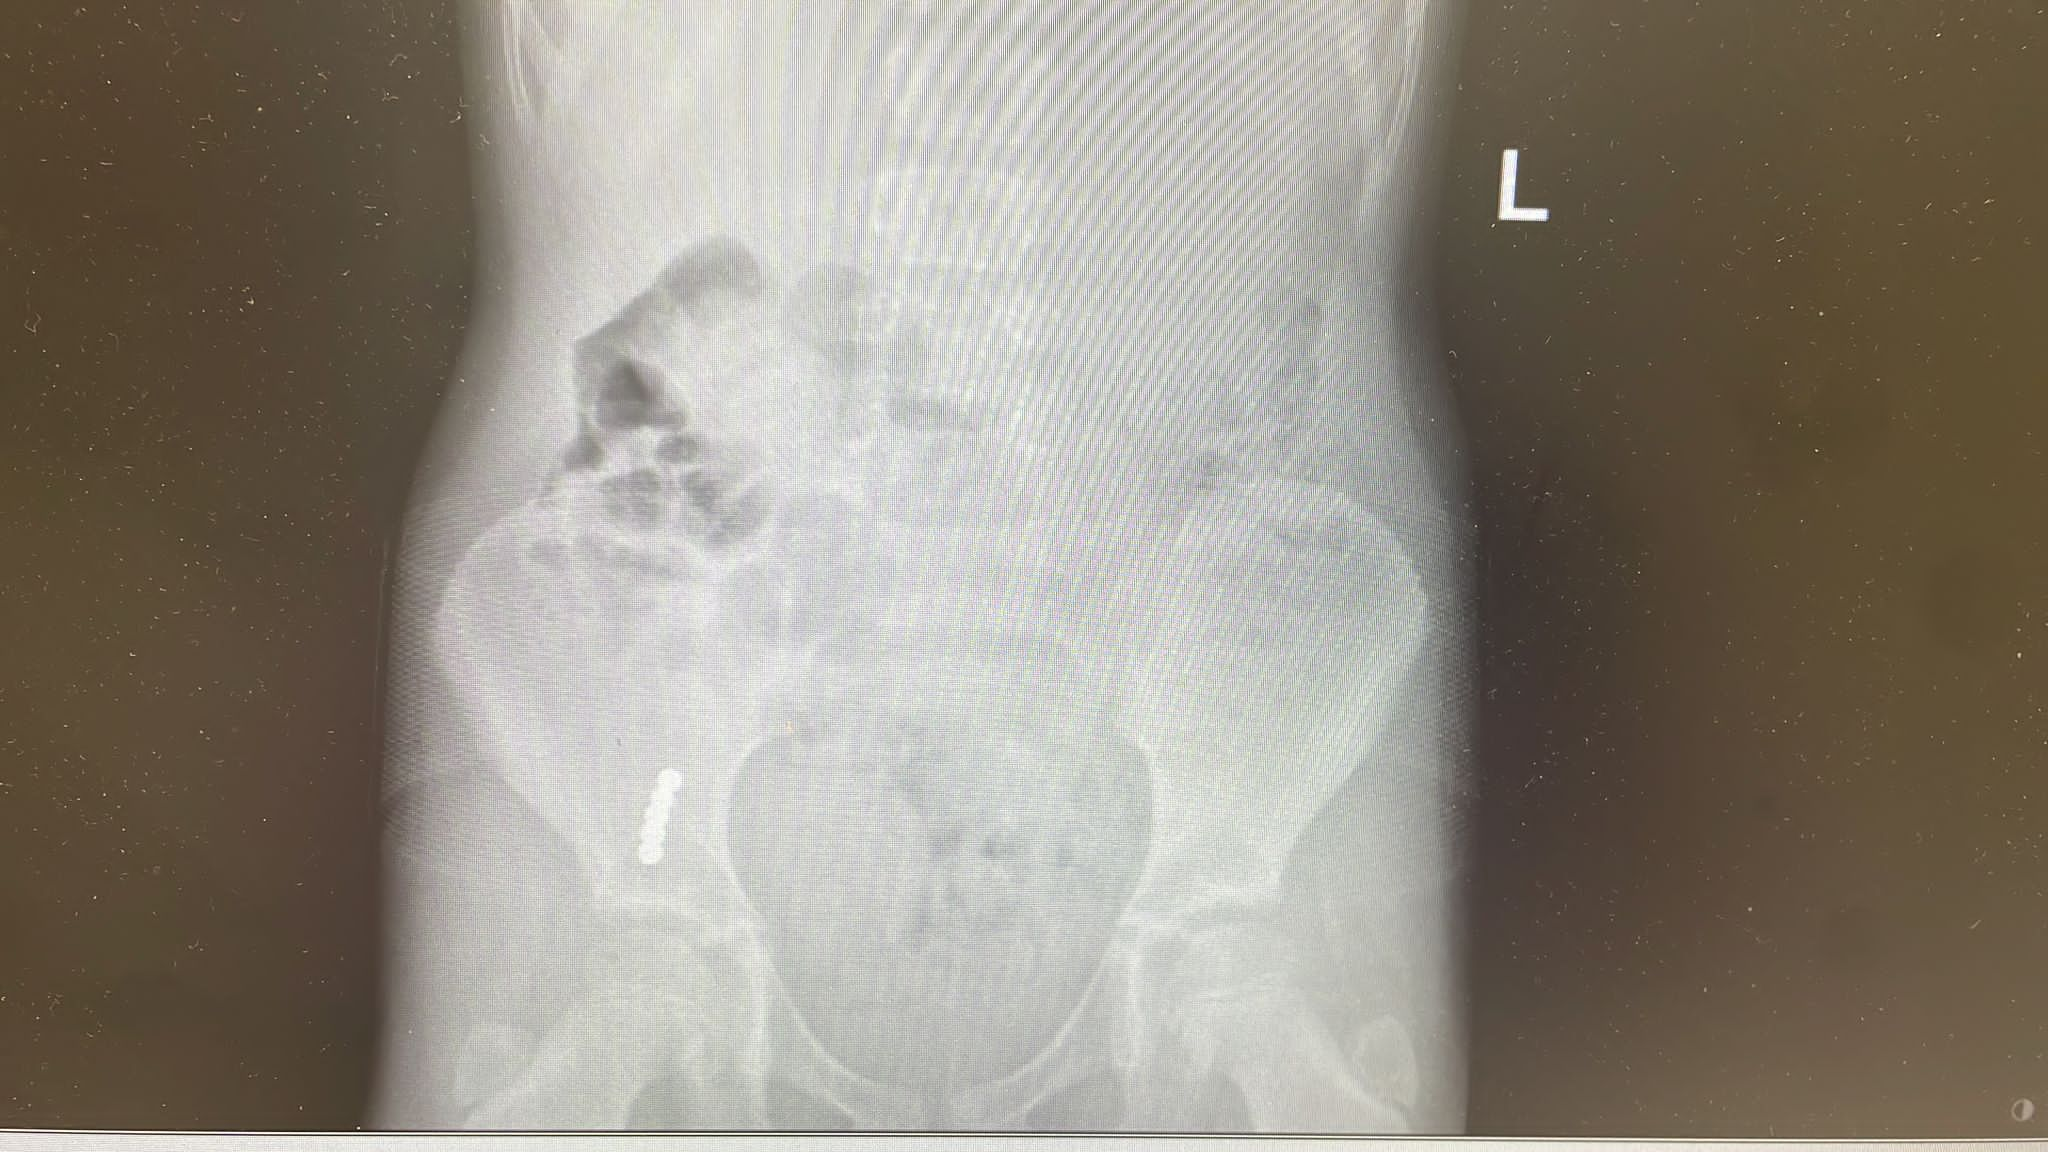

לעומתם, בצילומי רנטגן בילדה בת 7, נמצא כי חלקי המשחק שבלעה התמקמו במעי וגם לאחר 72 שעות טיפול לא הייתה התקדמות בניסיונות לחלץ את חלקי המשחק מגופה ולא נראתה אפשרות ליציאה באופן טבעי.

אאג/ניתוחי ראש צוואר ועם רופאים בכירים נוספים, הוחלט כי יש צורך בניתוחים דחופים כדי למנוע סכנה לחייהם של שני הילדים.

הניתוח הראשון, של הילדה בת ה 4, נעשה בראשותם של ד"ר עופר גליק וד"ר ירדן טננבאום ממחלקת א.א.ג/ניתוחי ראש צוואר; הניתוח השני, של הילדה בת ה 7, נעשה הבוקר (יום ד) על ידי ד"ר חני טאף. לשמחת כולם, הניתוחים הסתיימו בהצלחה. מטבעות הכסף וחלקי המשחק הוצאו בשלמותם והילדות הועברו להמשך טיפול והשגחה במחלקת הילדים של ביה"ח הציבורי אסותא אשדוד.